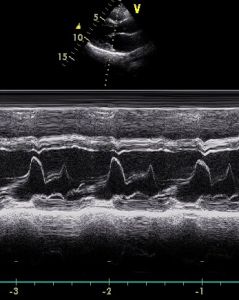

②測量法及觀察內容:M型心動超聲圖二尖瓣區E峰A峰FG段CD段

A.二尖瓣前葉運動幅度:二尖瓣曲線最低點(C點)之上緣到最高點(E點)之上緣之垂直距離(以下測幅度均同此法)。

B.二尖瓣前葉舒張早期關閉速度(EF速度)沿E至F段畫一向下延長線,沿E點向右畫一水平線,取相當1s之一段長度,在1s線末段畫一向下垂直線,與EF延線相交於一點,測量此點以上之垂直線長度,即為EF速度(mm/s)。以下凡測回聲速度,方法同此。

C.二尖瓣最大開放速度,即DE速度;

D.二尖瓣關閉速度,即AC段速度;

E.二尖瓣前葉A峰速度,即A點至C點之垂直距離;

F.二尖瓣前葉A峰/E峰比值,即A峰幅度/CE幅度;

G.左室流出道寬,二尖瓣前葉C點到室間隔左室面之距離;

H.觀察二尖瓣回聲(內容同主動脈瓣)。注意前葉後有無回聲團,左室流出道內有無絨毛狀回聲。